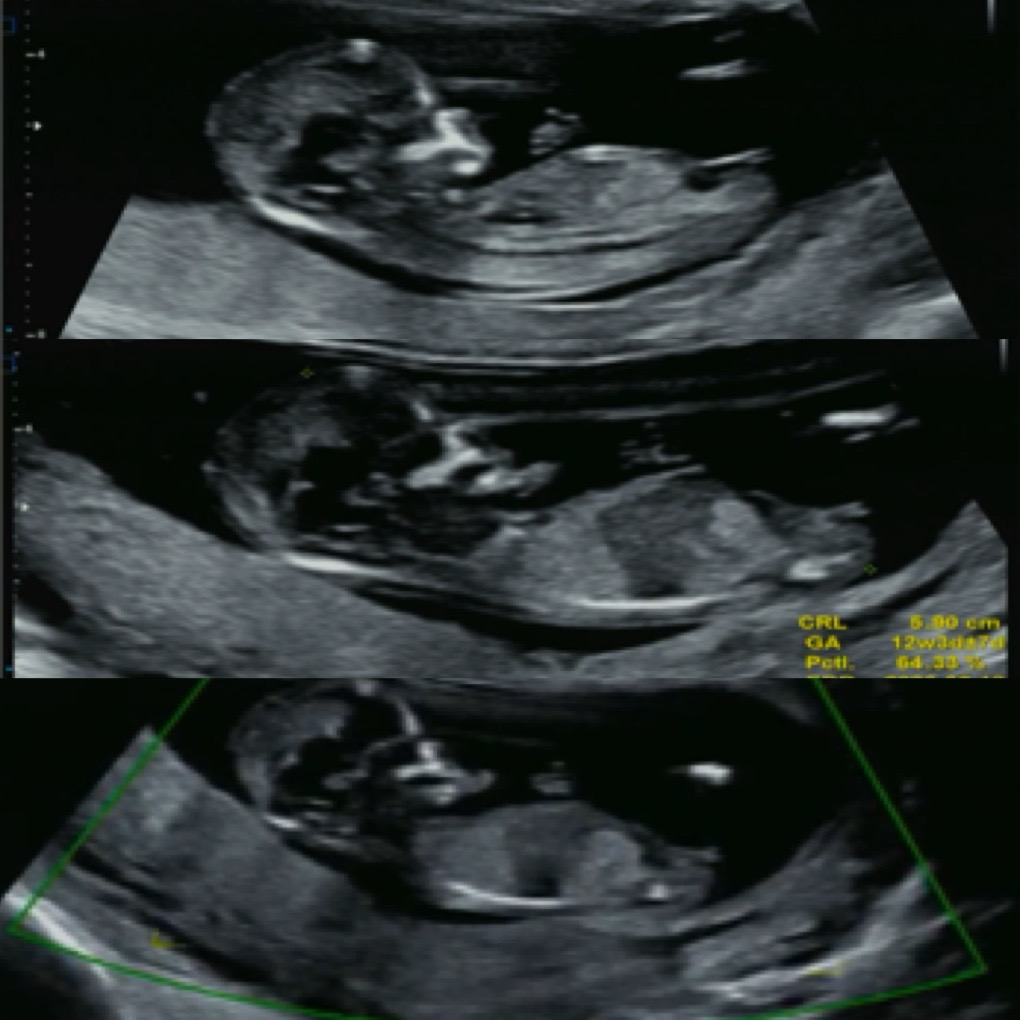

12주차 초음파사진인데 성별 각도법 궁금합니다

선배님들 의견이 궁금합니다. 각도법으로 아들일거 같나요 딸일거 같나요? 한달 뒤에 성별을 알수있겠지만 너무 궁금해요😂